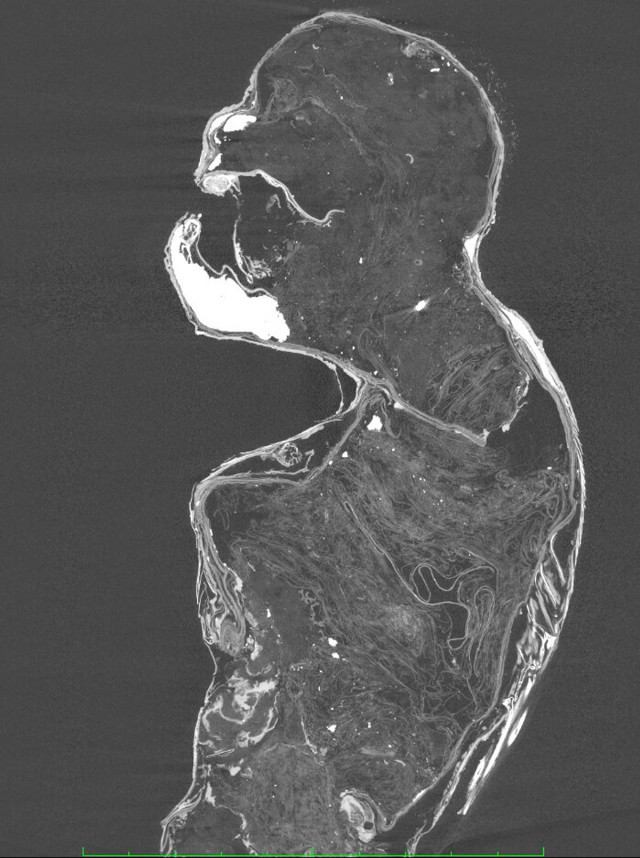

Дослідники з Університету науки і мистецтв Курасікі в Японії розкрили таємницю маленької мумії русалки, відомої, що зберігалася в храмі Ендзуін в Асакуті. Результати дослідження показали, що, на відміну від інших подібних зразків, верхня частина опудала була зроблена не з висушеної мавпячої плоті, а з паперу, тканини та бавовни.

Нижня частина опудала була зроблена з риб’ячого хвоста. Радіовуглецевий аналіз показав, що мумія була створена наприкінці 19 століття.

Знахідка дослідників з Університету Курасікі відрізняється тим, що для верхньої частини опудала використали папір, тканину й бавовну, що є доволі незвичним. Водночас саме опудало виглядає доволі реалістично, як і задумували творці фейку.